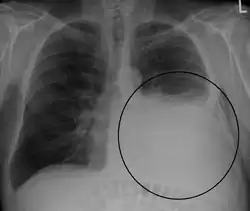

A pleural effusion appears as an area of whiteness on a standard posteroanterior chest X-ray.[15] Normally, the space between the visceral pleura and the parietal pleura cannot be seen. A pleural effusion infiltrates the space between these layers. Because the pleural effusion has a density similar to water, it can be seen on radiographs. Since the effusion has greater density than the rest of the lung, it gravitates towards the lower portions of the pleural cavity. The pleural effusion behaves according to basic fluid dynamics, conforming to the shape of pleural space, which is determined by the lung and chest wall. If the pleural space contains both air and fluid, then an air-fluid level that is horizontal will be present, instead of conforming to the lung space.[16] Chest radiographs in the lateral decubitus position (with the patient lying on the side of the pleural effusion) are more sensitive and can detect as little as 50 mL of fluid. Between 250 and 600mL of fluid must be present before upright chest X-rays can detect a pleural effusion (e.g., blunted costophrenic angles).[17]

Massive left-sided pleural effusion (whiteness) in a patient presenting with lung cancer. -